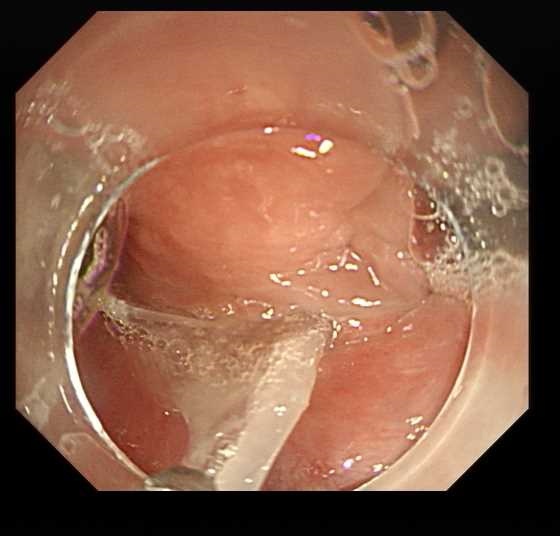

随即,老人被送往了内镜室。操作前,许医生深吸一口气,平稳地拿起胃镜。当内镜抵达食管上段时,显示屏上清晰地显示出那根致命凶器——鱼刺像一枚钉子深深扎入食管壁,距离颈动脉仅有毫厘之差。

“异物钳!”许医生冷静地指挥着。钳子在他的精准操控下,稳稳夹住鱼刺暴露的一端,轻柔而果断地向外拔出。整个过程只用了30秒,这根危及生命的鱼刺就被成功取出!